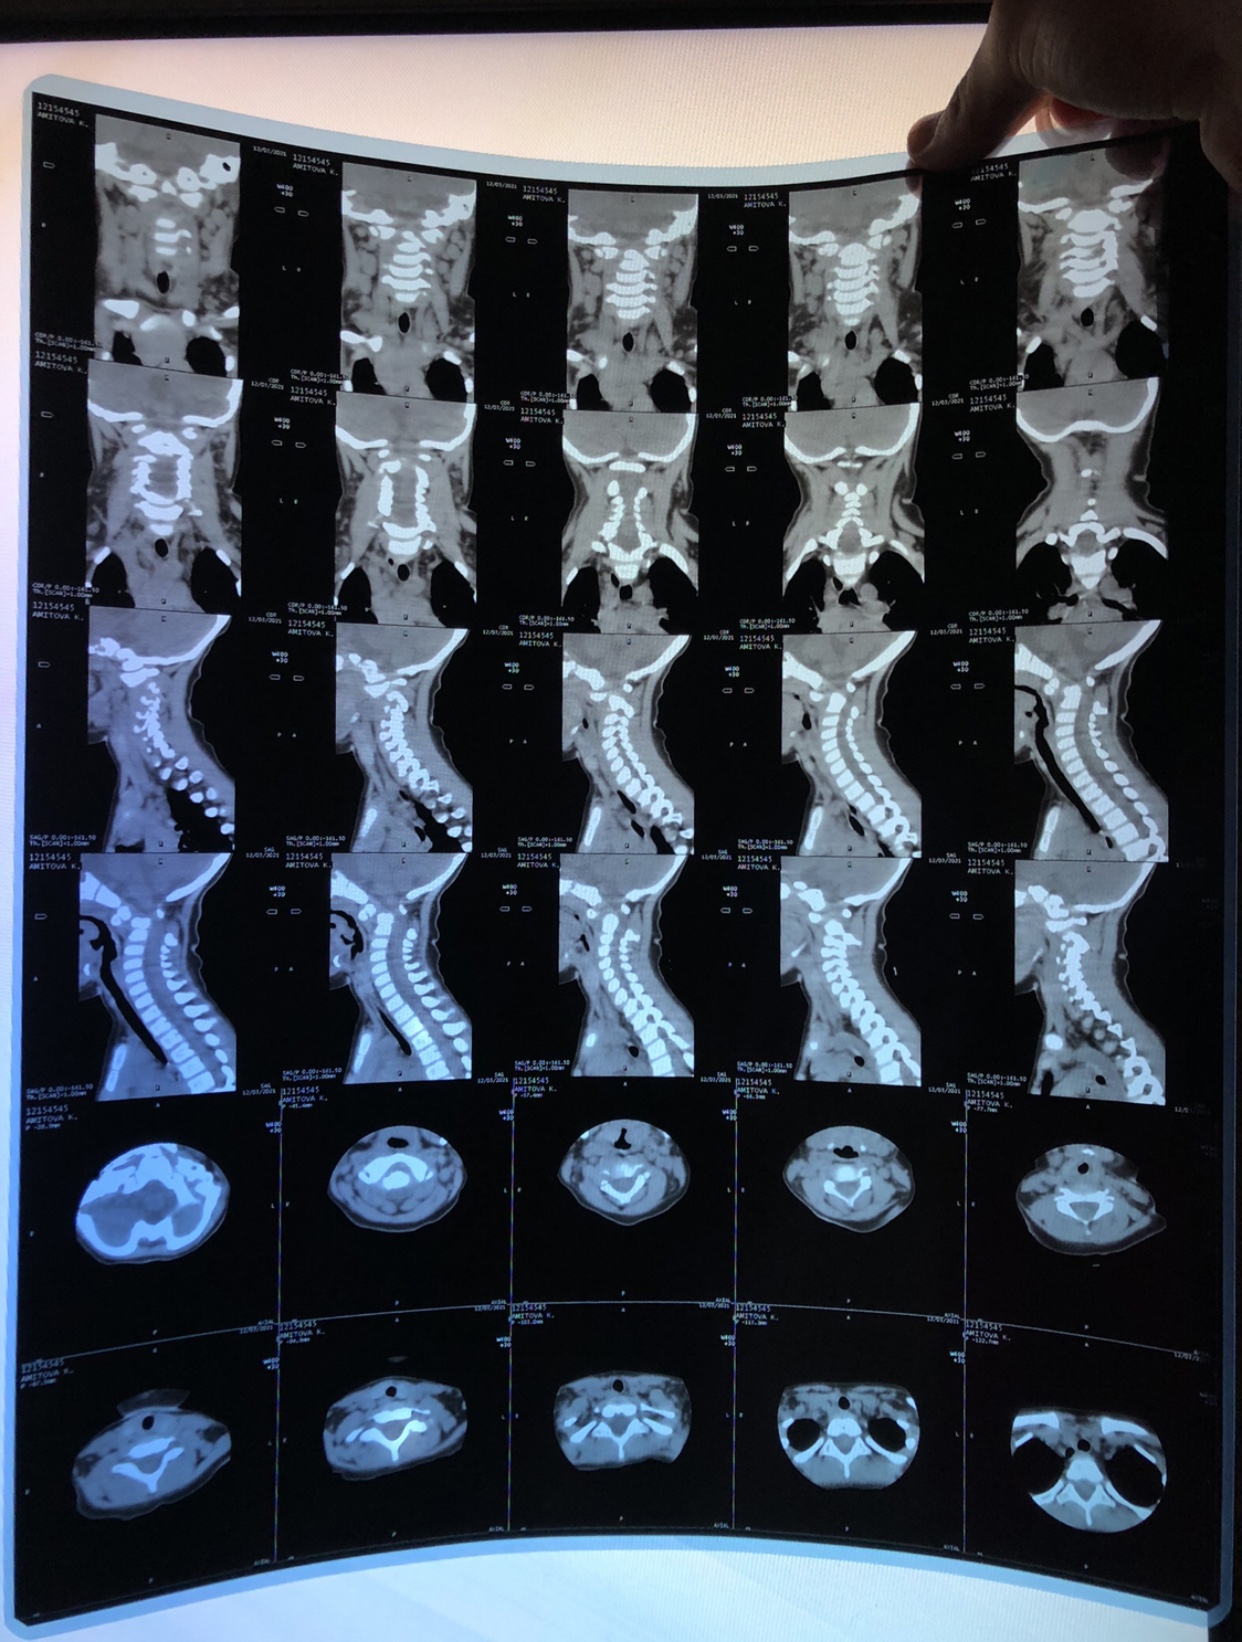

Провели кт шеи и мрт головы.

Показала заключения нейрохирургу клинической детской больницы и неврологу в частной клинике.

Патологий не обнаружено по снимкам и на днях отправила в Москву даунсайдап. На что получила ответ по моему запросу. Сказали срочно нужно прооперировать в связи нестабильностью позвонков.